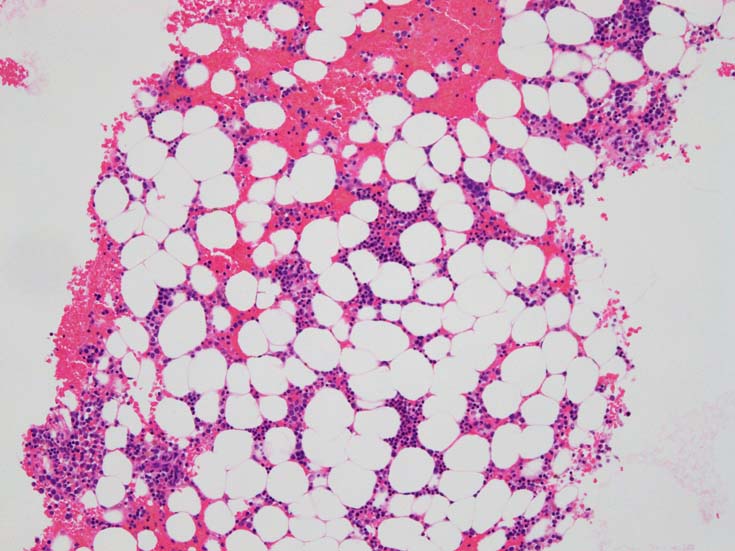

骨髄赤芽球のHbF発現

MDS症例のHbF発現.

サムネイル画像をクリックすると大きな画像が見られます.

MDSでの赤芽球HbF発現は, 陽性細胞はそれほど多くない印象ですが, この低形成性MDS症例では, 多くの陽性細胞がaggregatesを形成していました.